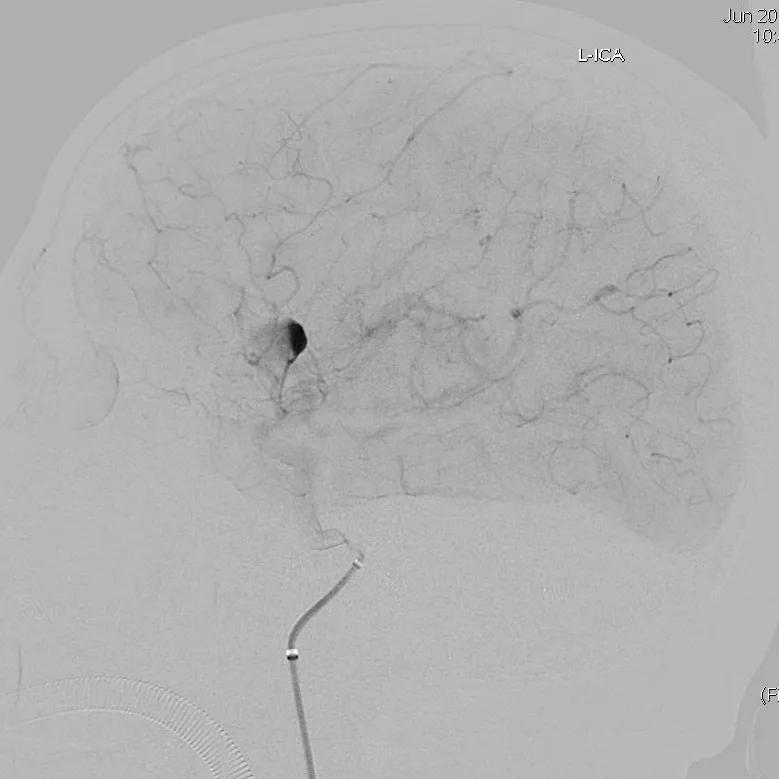

患者于入院前1天无明显诱因突发头。外院头颅CTA示:颅内动脉瘤。我院行DSA示:左侧大脑中动脉动脉瘤。

全脑血管造影可见左侧大脑中动脉动脉瘤,瘤体最大径:16.7mm,瘤颈宽:8.3mm。

Synchro 14微导丝导引支架导管,远端送入左侧中动脉下干远端困难,支架导管内穿行Tracxseed微导丝,双导丝导引支架导管顺利进入左侧中动脉下干远端,尾部链接Y阀1个,压力带1个。

经支架导管,置入Tubridge® 3.0×30mm,释放位置良好。

复查造影,动脉瘤造影剂明显滞留,各血管及分支通畅,流速正常。手术结束。